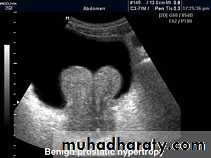

PROSTATIC Enlargement

Common cause of lower urinary obstruction . Either Benign prostatic hyperplasia or Carcinoma .Benign Hyperplasia :-

* US can distinguish between BPH & Ca.